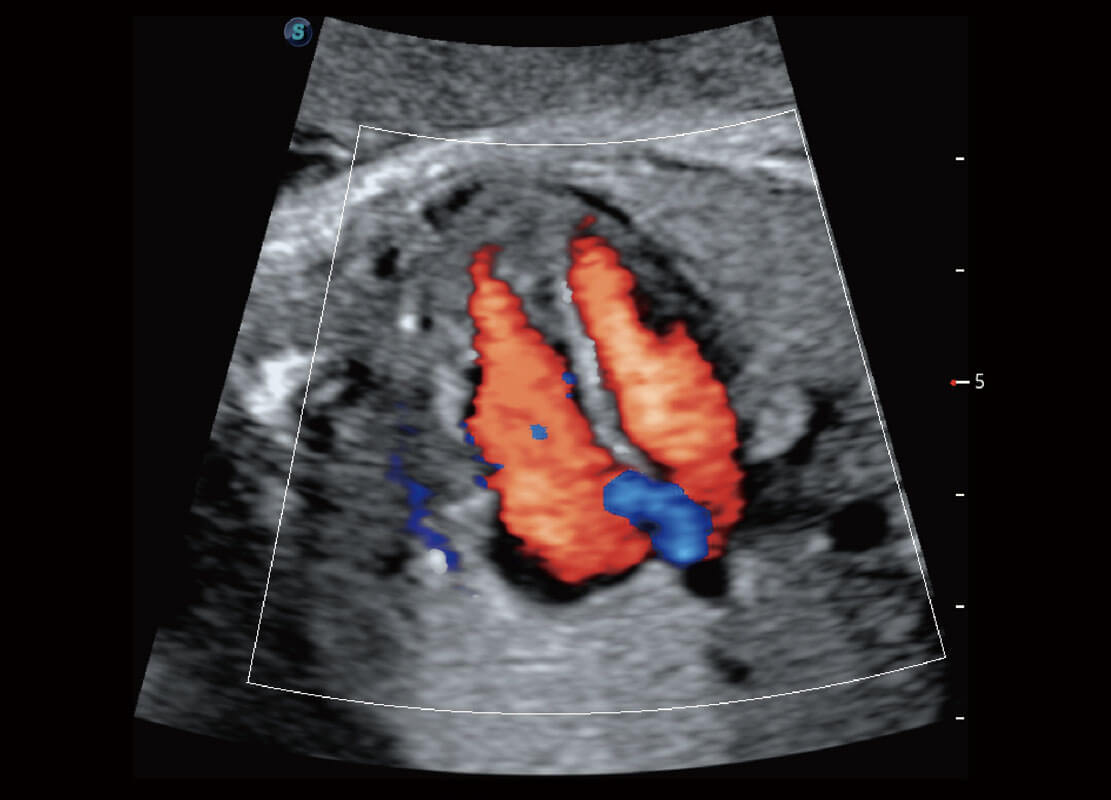

P60优异的图像质量搭载专科探头,在妇科基础疾病的诊断、卵泡生长的监测、输卵管通畅情况的判别等方面为您提供生殖应用方案。

腔内妇科-宫腔分离

腔内妇科-卵巢